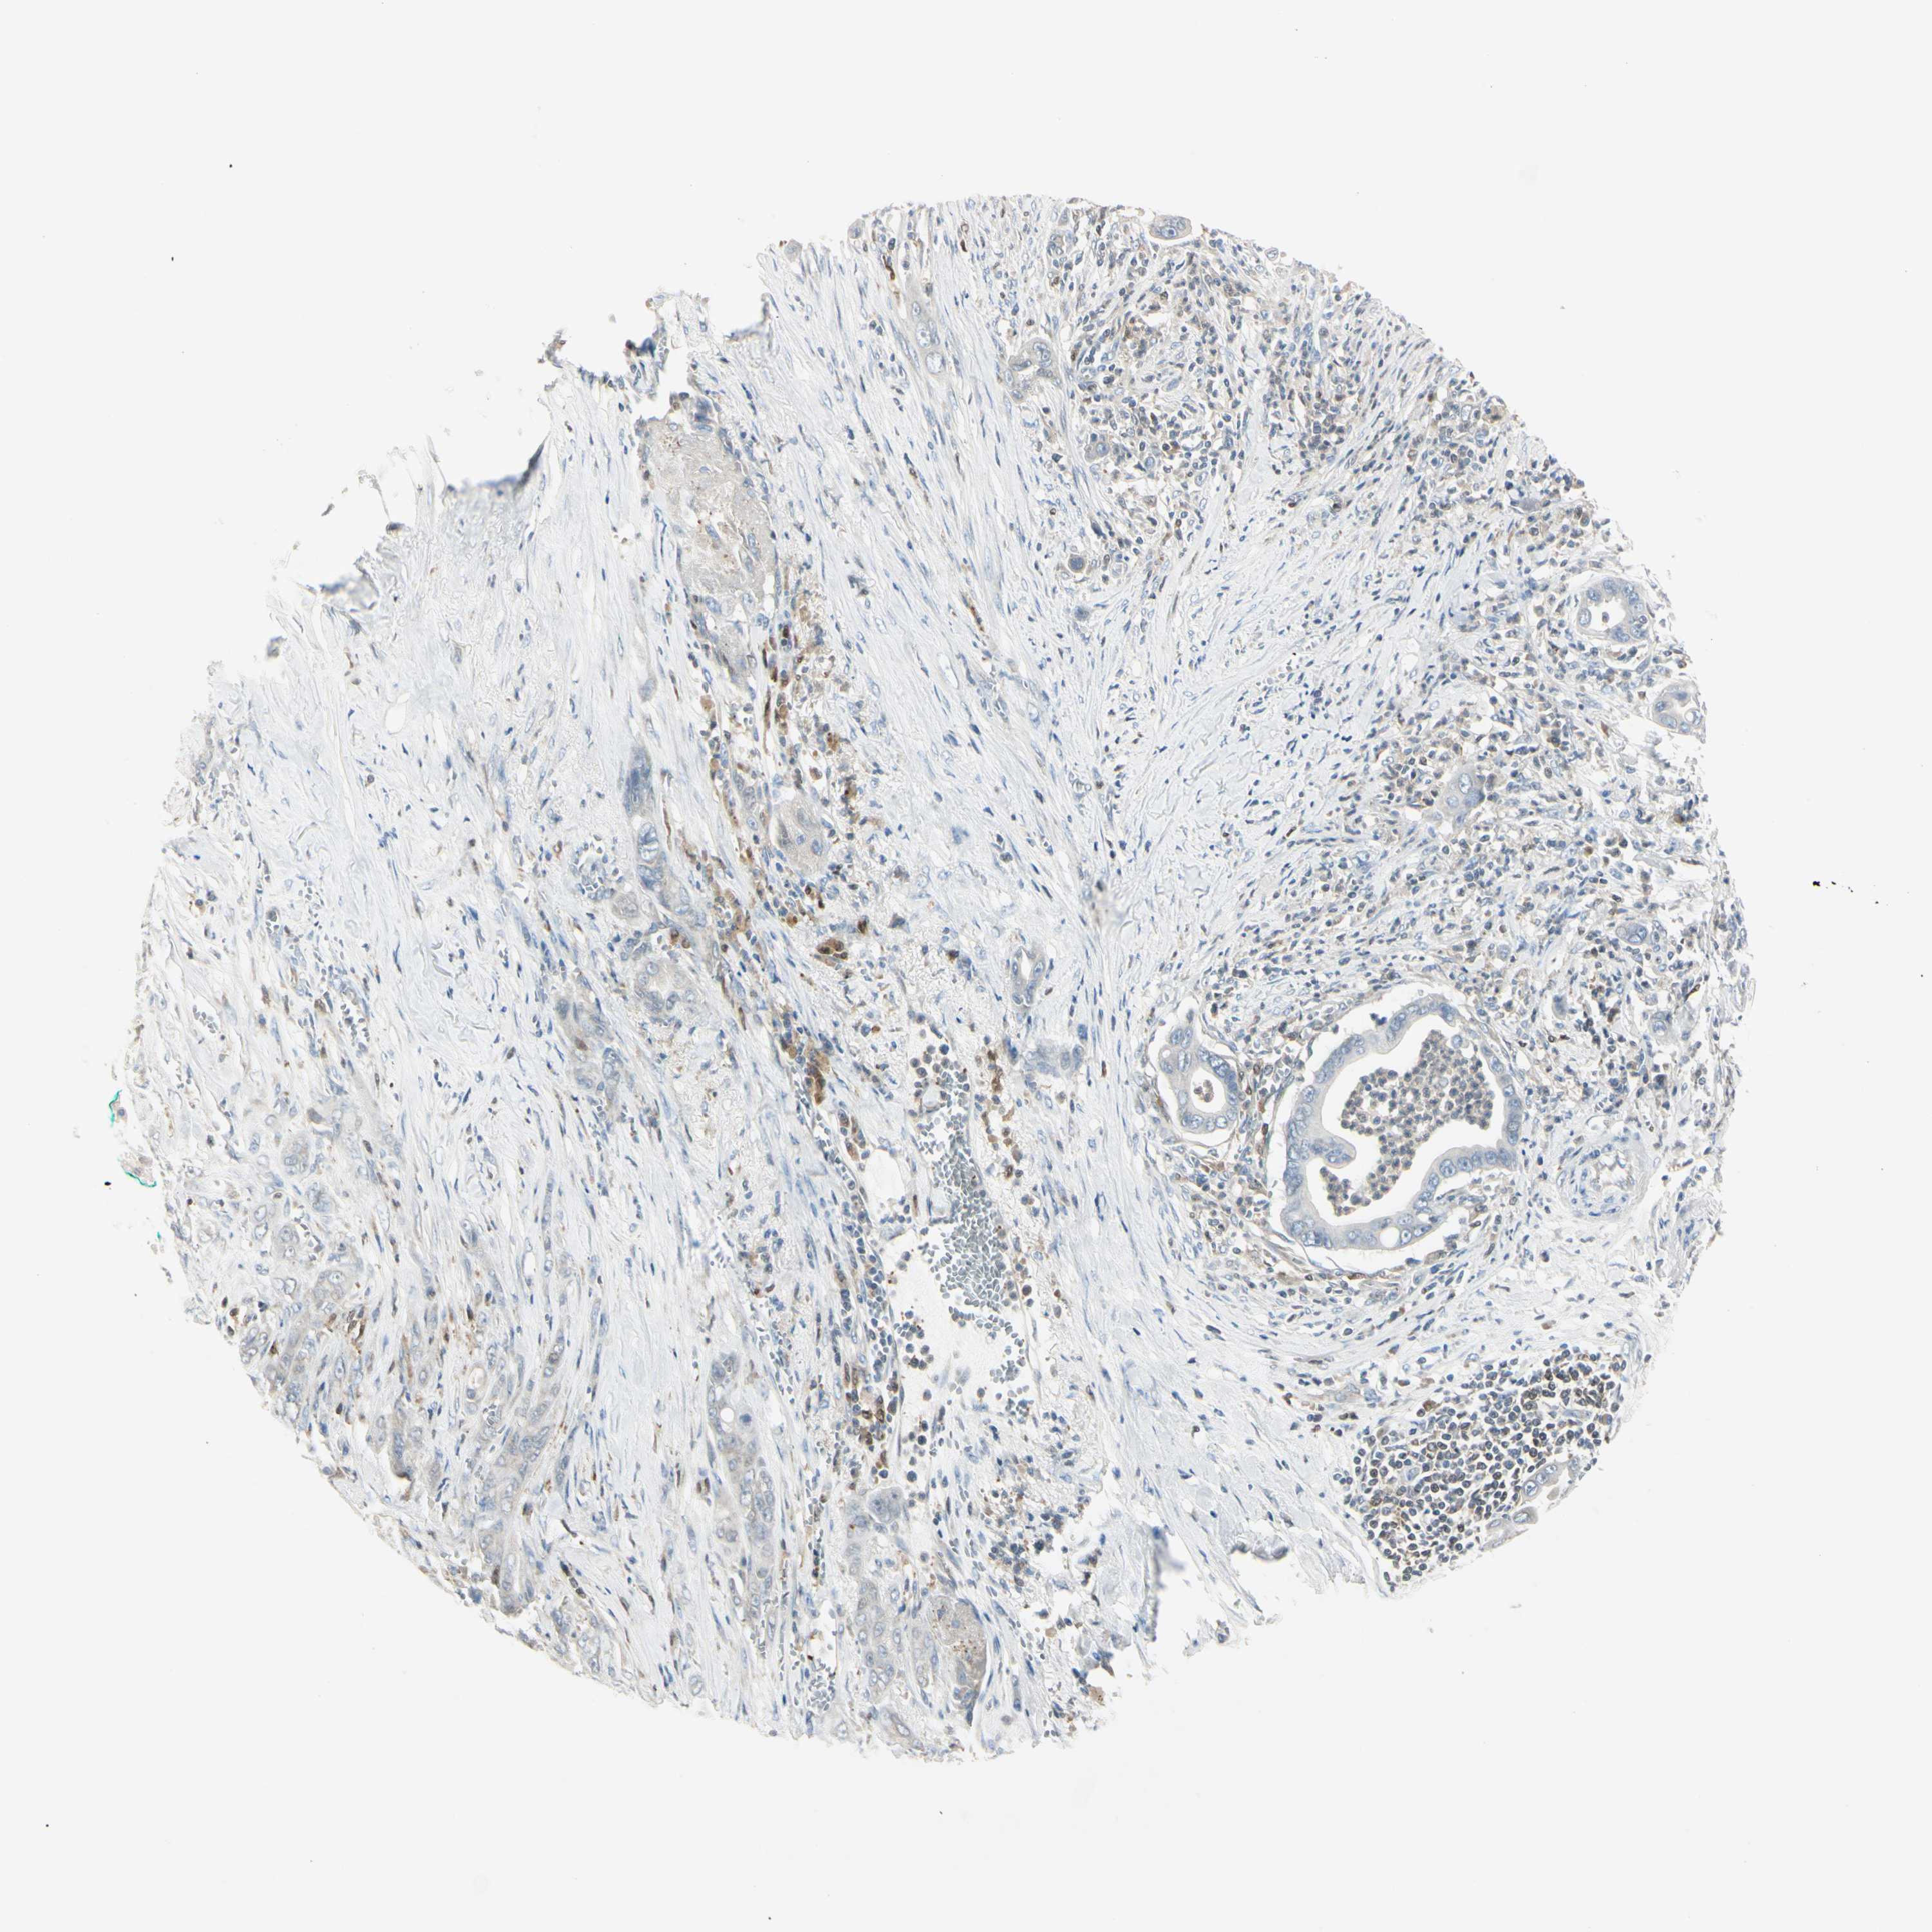

PANCREATIC CANCER - Protein expressioni

A mouse-over function shows sample information and annotation data. Click on an image to view it in a full screen mode. Samples can be filtered based on level of antibody staining by selecting one or several of the following categories: high, medium, low and not detected. The assay and annotation is described here.

Note that samples used for immunohistochemistry by the Human Protein Atlas do not correspond to samples in the TCGA dataset.

Antibody stainingi

Antibody staining in the annotated cell types in the current human tissue is reported as not detected, low, medium, or high, based on conventional immunohistochemistry profiling in selected tissues. This score is based on the combination of the staining intensity and fraction of stained cells.

Each image is clickable and will lead to virtual microscopy that enables deeper exploration of all samples and also displays staining intensity scores, fraction scores and subcellular localization as well as patient and tissue information for each sample.

Antibody HPA009076

Staining

High

Medium

Low

Not detected

Intensity

Strong

Moderate

Weak

Negative

Quantity

>75%

75%-25%

<25%

None

Location

Nuclear

Cytoplasmic/membranous

Cytoplasmic/membranous,nuclear

Adenocarcinoma, NOS

Adenocarcinoma, metastatic, NOS